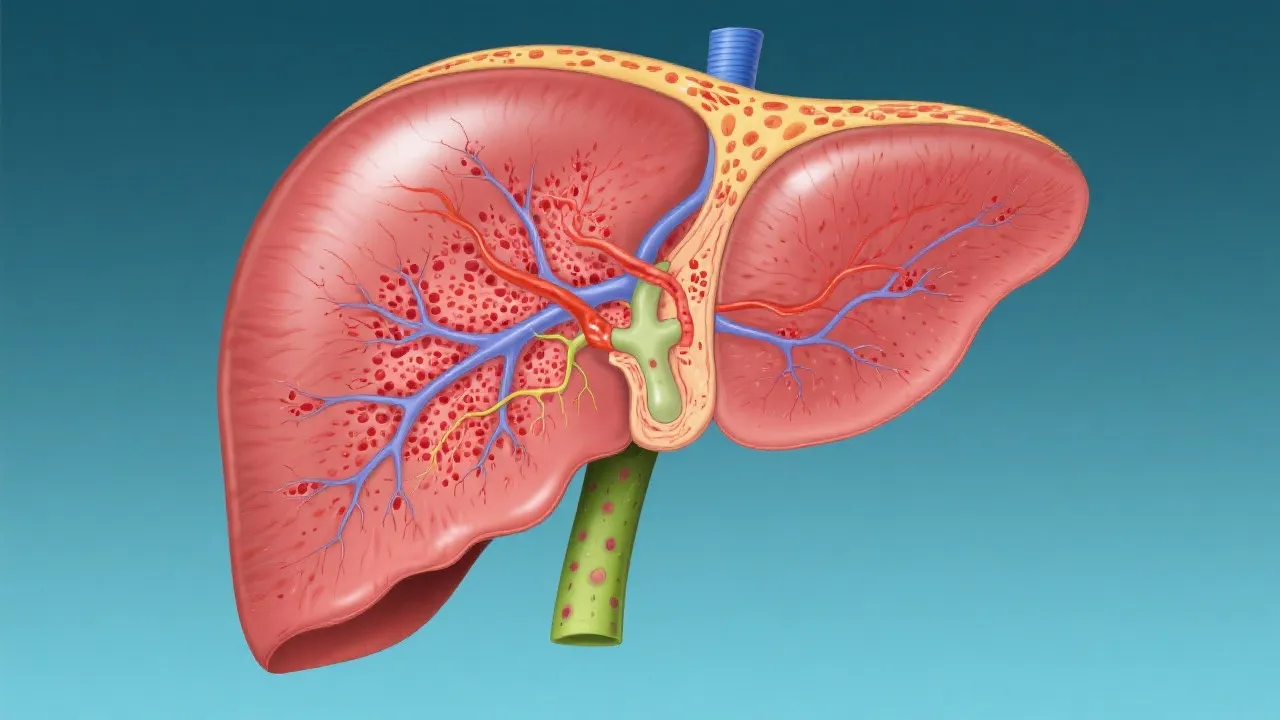

Understanding Hepatitis E and Liver Transplant

Understanding Hepatitis E and Liver Transplants

Understanding Hepatitis E and Liver Transplants

Understanding Hepatitis E and Liver Transplants

Understanding Hepatitis E and Liver Transplants

Hepatitis E and Liver Transplant

Understanding Hepatitis E and Liver Transplant

Understanding Hepatitis E and Liver Transplants

Navigating Hepatitis E and Liver Transplant

Navigating Hepatitis E Liver Transplants

Hepatitis E and Liver Transplant Insights

Hepatitis E and Liver Transplant